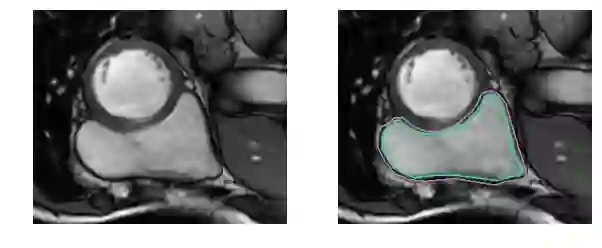

下面用几组图片来感受一下这种分割问题的困难。下图是右心室的MRI图片:

再困难一点: